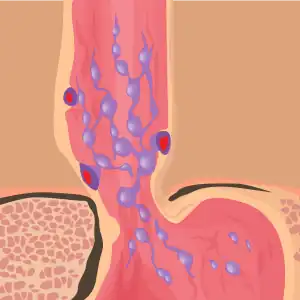

Drawing of esophageal varices at the esophageal gastric junction

Esophageal varices are dilated veins under the mucosa in the lower third of the esophagus.[1][3] The first symptom is generally GI bleeding, with vomiting blood, red blood per rectum, or black blood per rectum.[1] Associated symptom may include itchiness, weight lose, and yellowish skin.[1]